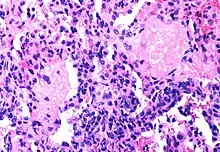

Only a small number of CD4+ T-cells are infected by HIV, not enough to damage the immune system

Although the fraction of CD4+ T-cells that is infected with HIV at any given time is never high (only a small subset of activated cells serve as ideal targets of infection), several groups have shown that rapid cycles of death of infected cells and infection of new target cells occur throughout the course of the disease.[41] Macrophages and other cell types are also infected with HIV and serve as reservoirs for the virus.

Furthermore, like other viruses, HIV is able to suppress the immune system by secreting proteins that interfere with it. For example, HIV's coat protein, gp120, sheds from viral particles and binds to the CD4 receptors of otherwise healthy T-cells; this interferes with the normal function of these signalling receptors. Another HIV protein, Tat, has been demonstrated to suppress T cell activity.

Infected lymphocytes express the Fas ligand, a cell-surface protein that triggers the death of neighboring uninfected T-cells expressing the Fas receptor.[42] This "bystander killing" effect shows that great harm can be caused to the immune system even with a limited number of infected cells.